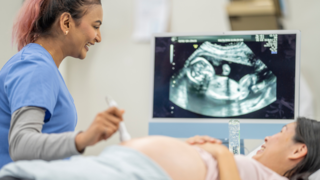

Pregnancy can be an exciting journey with a lot of emotional, physical and mental changes as your body prepares to bring a new life into the world. Each stage of pregnancy comes with its own set of challenges and joys. Whether you are trying to understand the new symptoms or learning about prenatal care, we have got you covered. You will get all the information on nutrition, health tips, and emotional well-being that will be valuable for you and your unborn baby so you can adapt to this new journey with joy, happiness, and knowledge.

Why Babies Grow in Spurts Instead of a Straight Line Inside the WombOnce you get pregnant, your baby’s growth doesn’t always happen in a consistent manner. Rather, they grow in spurts, periods of rapid development followed by slower phases. This is a usual pattern and crucial for healthy development. Knowing why babies follow such a growth pattern during pregnancy can make you feel calmer during ultrasounds. It also helps you understand what to expect about your baby’s size and weight. It can also assist you in taking better care of yourself, both physically and emotionally.